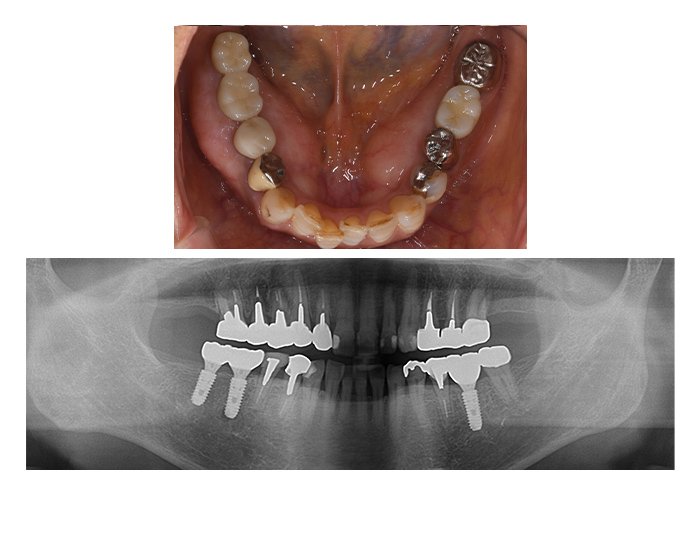

症例04 奥歯のインプラント6本(女性、期間9カ月)

BEFORE(術前)

AFTER(術後)